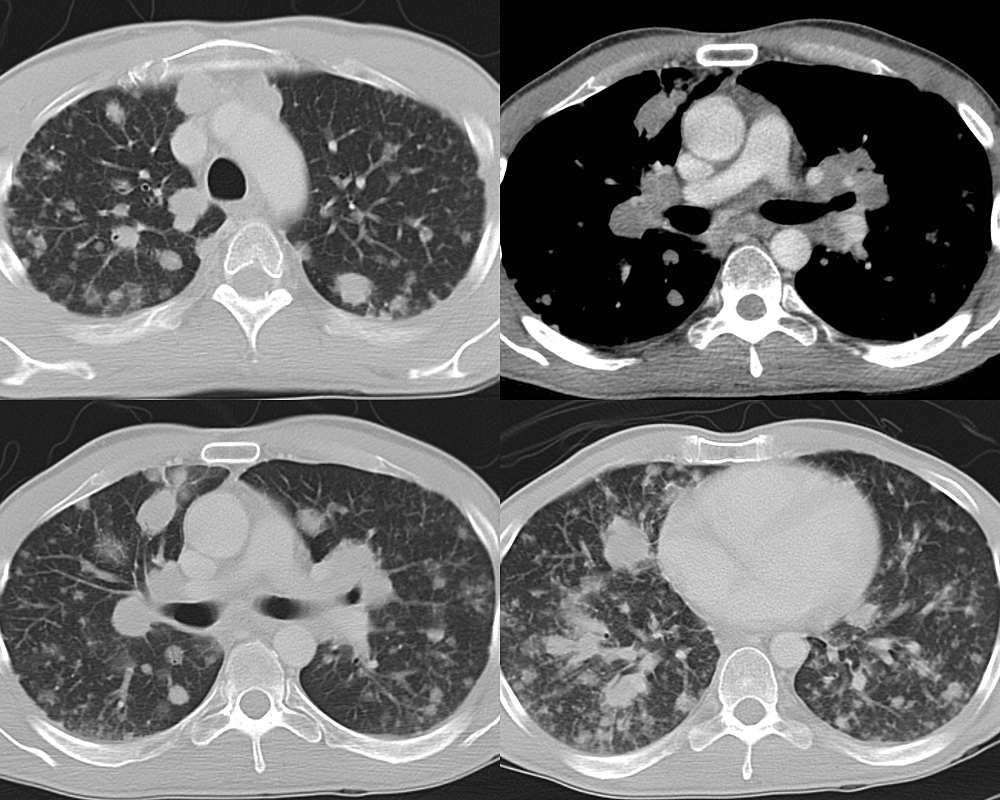

Mediastinum

Lymphoma

NHL